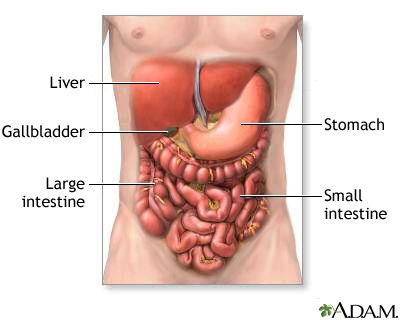

A hepatic hemangioma is a liver mass made of widened (dilated) blood vessels. It is not cancerous.

A hepatic hemangioma is the most common type of liver mass that is not caused by cancer. It may be a birth defect.

In most cases, the condition is not found until liver images are taken for some other reason. If the hemangioma ruptures, the only sign may be an enlarged liver.

- A growth in the abdomen